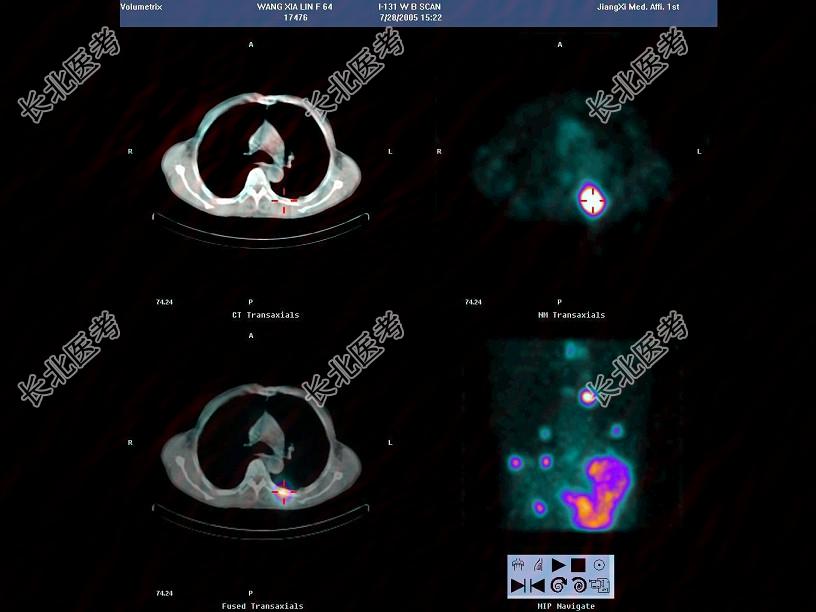

多项选择题63岁男性,甲状腺滤泡状癌术后3年, 行I全身显像及SPECT/CT图像融合如图,正确的诊断是 ( )

A、多发肺、脑转移

B、有骨转移

C、无骨转移

D、多发肺转移

E、未见明显转移灶